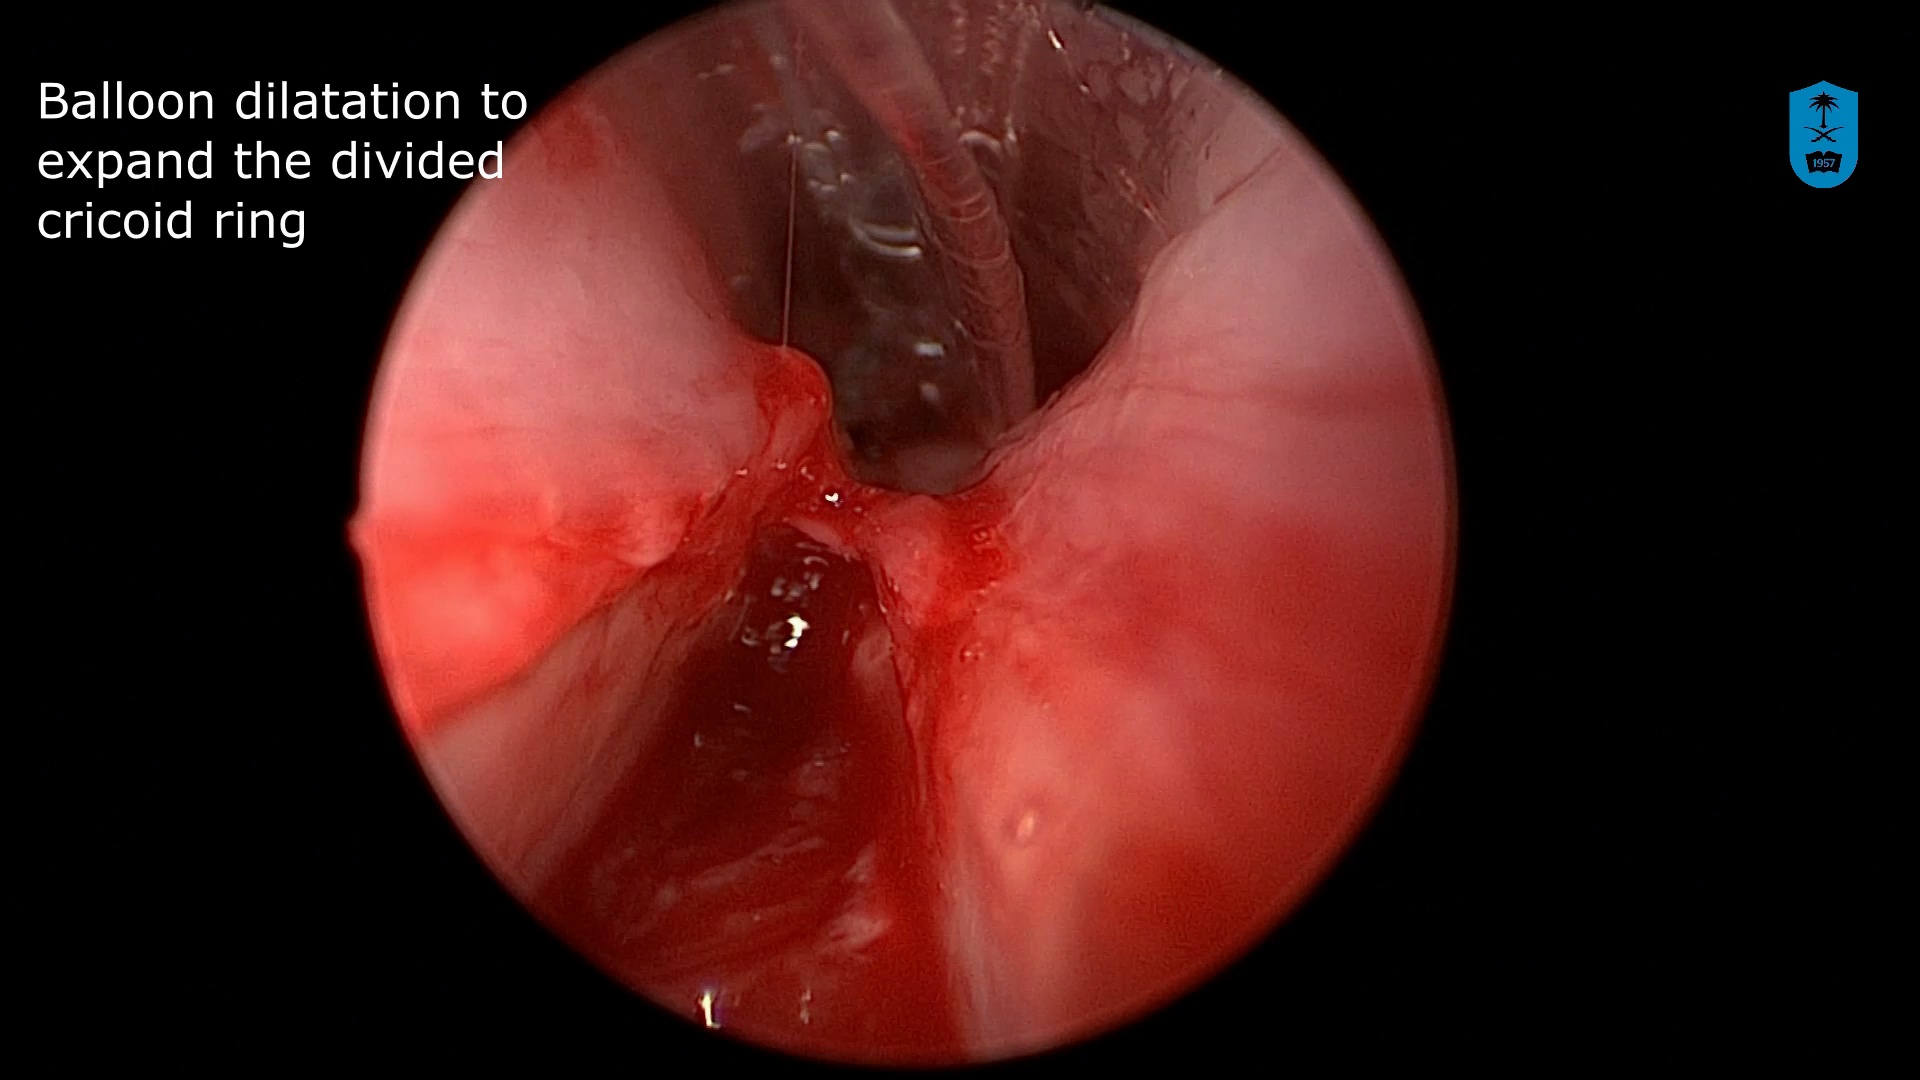

Watch the Full VideoIntroduction: Cricopharyngeal dysfunction (CPD) is a spectrum disorder encompassing multiple entities that ultimately result in dysphagia as a result of disruption of the normal anatomy or physiology of upper esophageal sphincter. It is a known and well described cause of dysphagia in adults, however, it’s role in pediatric dysphagia is less clear and limited to mostly small case series.1 Despite it’s relatively low prevalence, the complex pediatric otolaryngologist must be aware of this entity and it’s management. We discuss a complex case of CPD with an associated cricopharyngeal bar and pharyngeal diverticulum, as well as our successful endoscopic surgical approach highlighting the principles of CPD management in children. Case Presentation: We present a 21 month of female with a history of DiGeorge Syndrome and oropharyngeal dysphagia. Despite appropriate conservative measures including feeding therapy and diet thickening modification, as well as attempted Botox injection, the patient continued to demonstrate dysphagia. It was also noted on her swallow study that she had a posteriorly based pharyngeal diverticulum that potentially served as an aspiration reservoir. The decision was made to proceed with endoscopic cricopharyngeal division and diverticulum marsupialization. Technique: With the patient intubated, a Lindholm laryngoscope was placed posteriorly into the hypopharynx, elevating the larynx and allowing visualization of the upper esophageal sphincter and isolation of the cricopharyngeal bar. A non- contact CO2 laser fiber at 2W continuous spray was then used to divide the cricopharyngeal bar layer by layer making sure to isolate the muscle and not create a pharyngotomy. Standard laser safety precautions were followed. Tension was maintained using a right-angle hook allowing for optimal laser division. This was continued until the entirety of the bar was divided. At this point, the posterior pharyngeal diverticulum was identified. Again, with the use of a right angle probe for traction and depth assessment, The anterior wall of the diverticulum was divided. This was continued until the diverticulum was fully marsupialized and in continuity with the posterior pharyngeal wall into the esophageal inlet. Post operatively the patient was extubated and observed overnight in the hospital Swallow study three weeks later demonstrated normalization of the flow of bolus through the UES as well as resolution of the previously seen diverticulum. Conclusion: Cricopharyngeal Dysfunction (CPD) is an uncommon but recognized cause of pediatric dysphagia with multiple treatment options of varying success. Endoscopic CO2 laser division is a viable and effective treatment option for this condition.